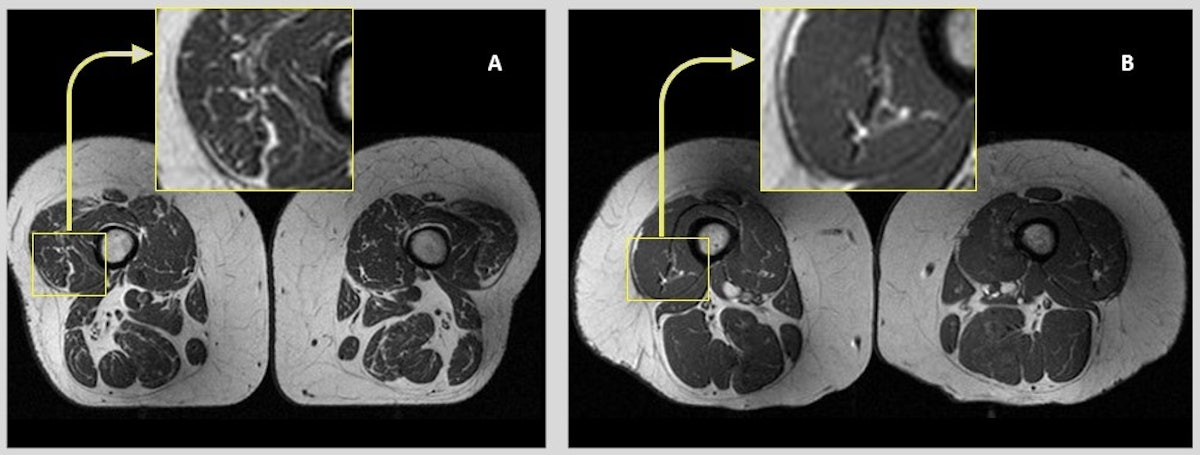

샌프란시스코 의대 연구팀은 MRI를 통해 초가공식품(라면, 햄버거, 피자, 프라이드치킨 등)을 자주 섭취한 사람들의 대퇴 근육에 지방 줄무늬가 더 많이 나타난다는 사실을 확인했다. (UCSF 연구, 2023)